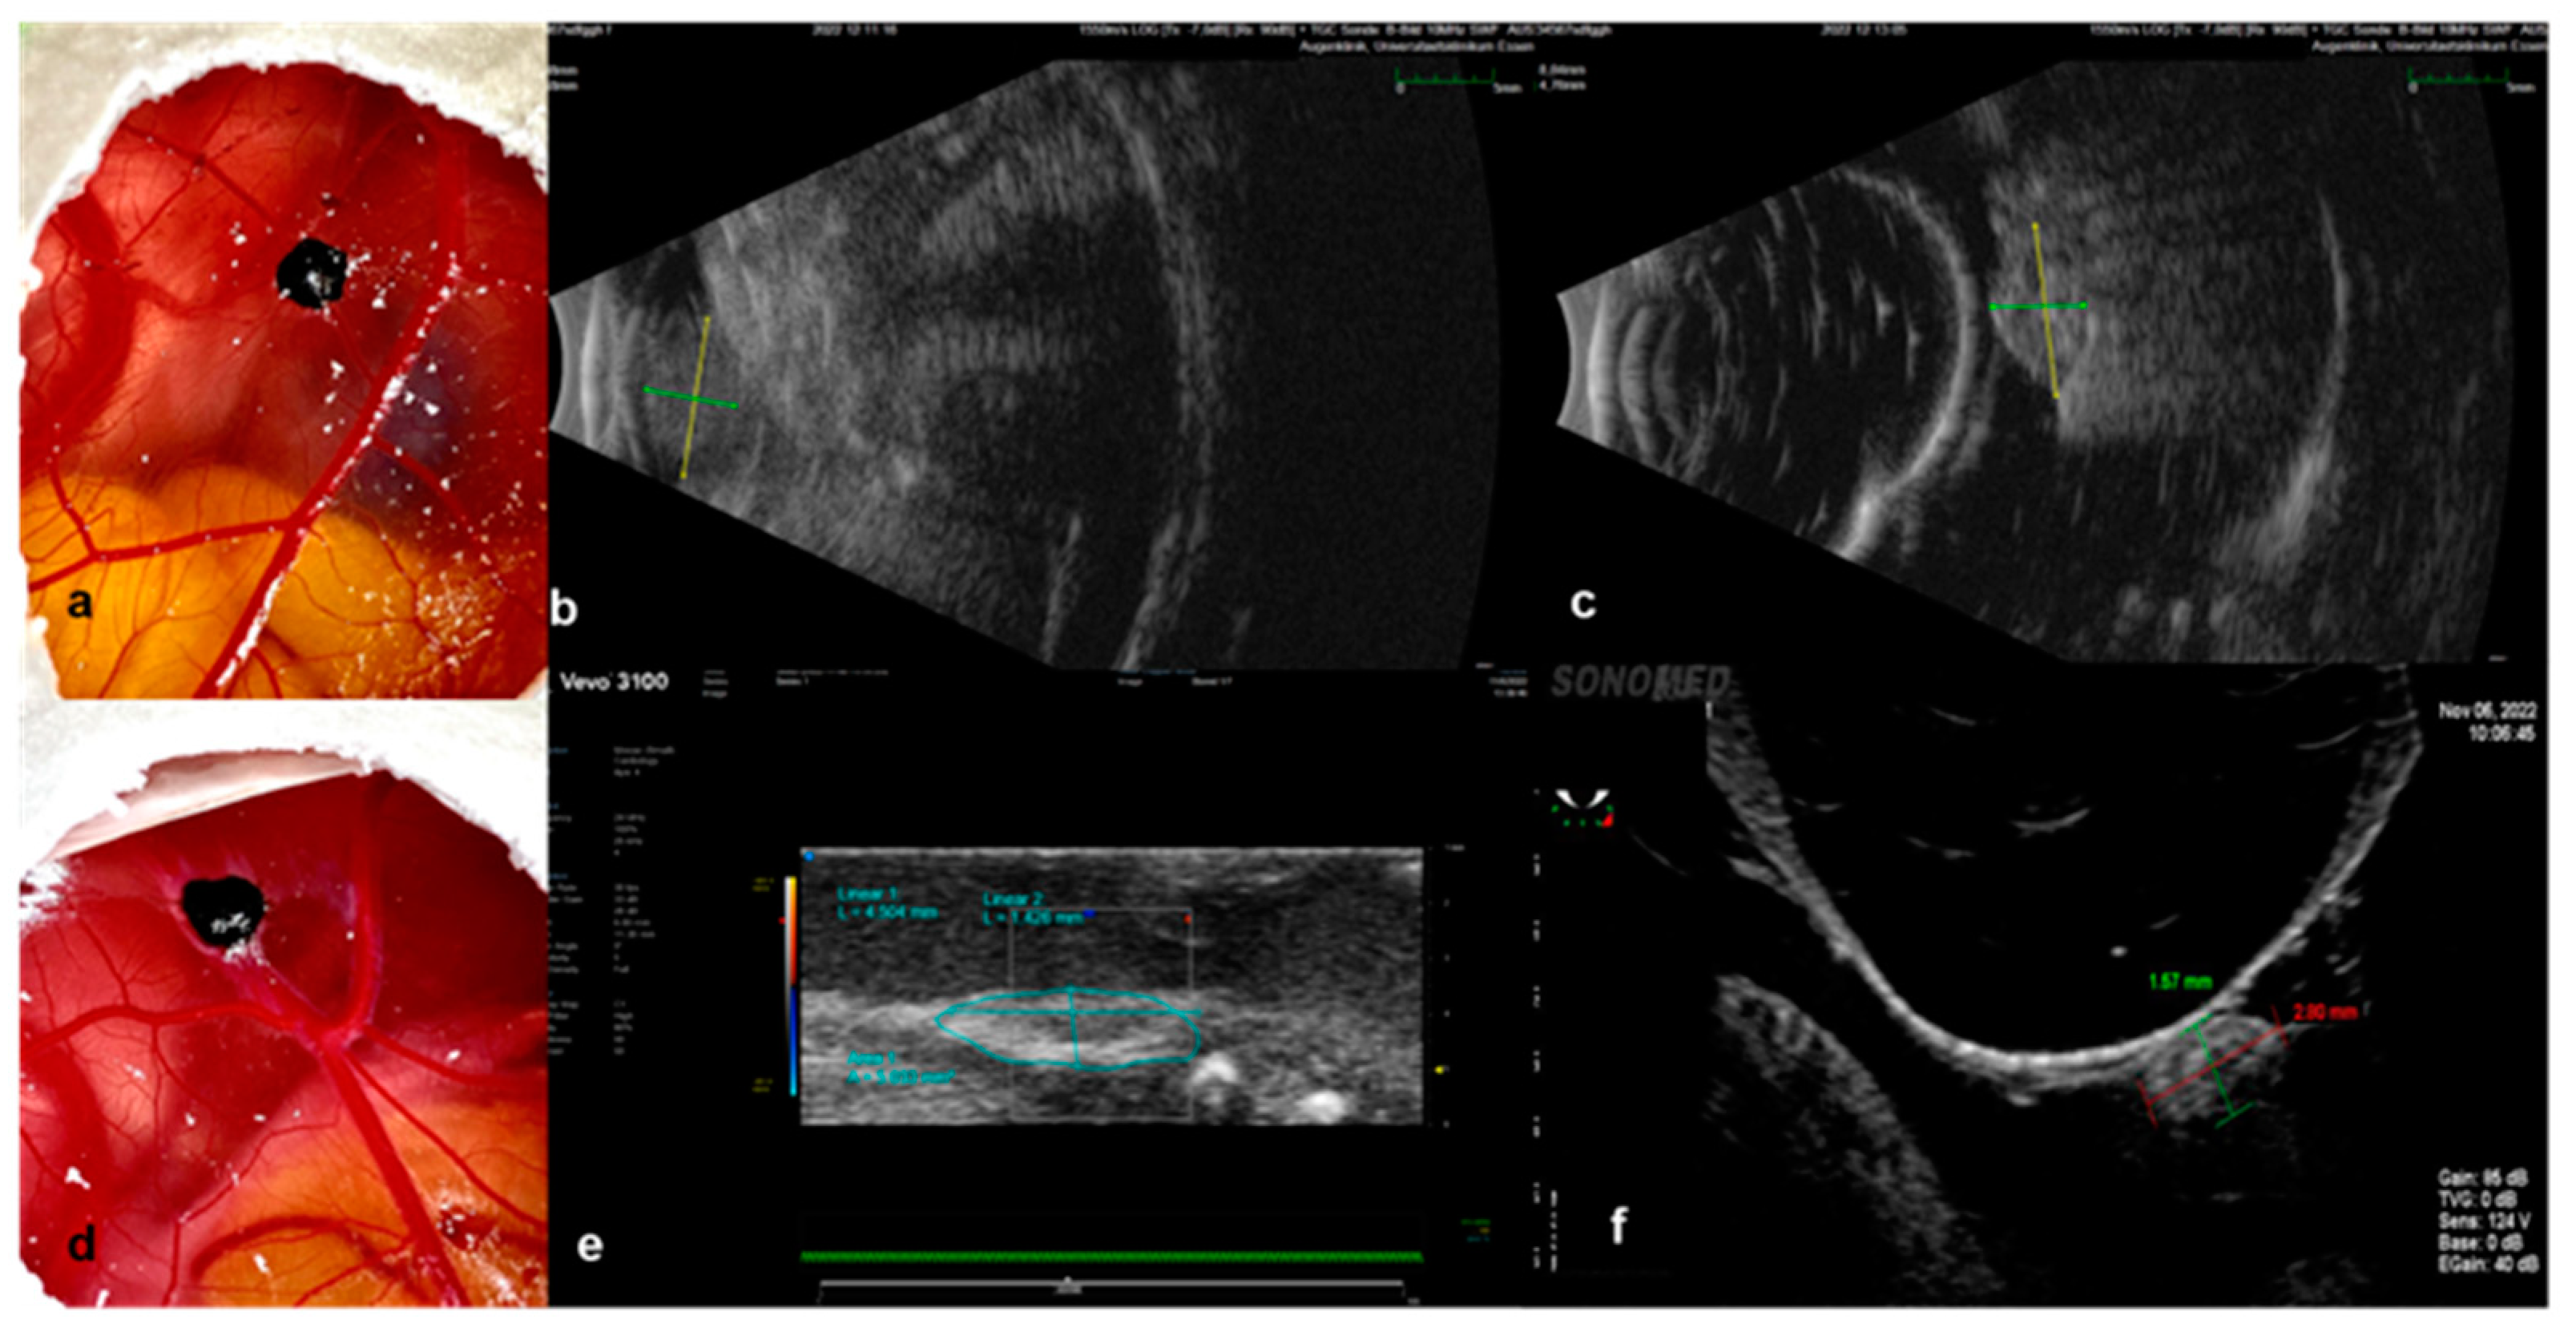

3.2.1. Ultrasound

3.2.2. Infrared Imaging, Optical Coherence Tomography and Angiography, and Fluorescein Angiography

2.4.1. Ultrasound